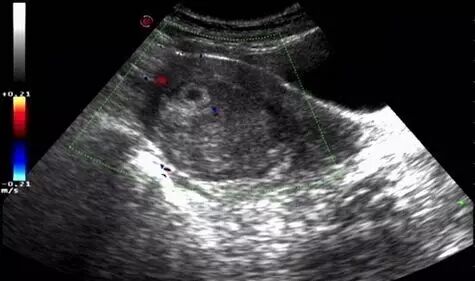

彩超显示暗区内有血流信号,四周呈放射状排列,原始胎盘区彩色血流显示极为丰富,脉冲多普勒在暗区内采样,可以获得静脉性频谱(流速约为0.02~0.05m/s)及动脉性频谱,舒张期成分非常丰富,阻力指数(RI)在0.45左右。双环征暗区内的血流称为滋养层周围血流(peritrophoblasticf)0w)。双环征的暗区内血流反映了子宫螺旋动脉向着床部位供应血液,满足妊娠囊生长发育所需,血池为胎盘循环的前身。滋养层周围血流的存在对早期妊娠至关重要,为判断早期妊娠是否良好提供重要的依据。妊娠10周后双环征消失。